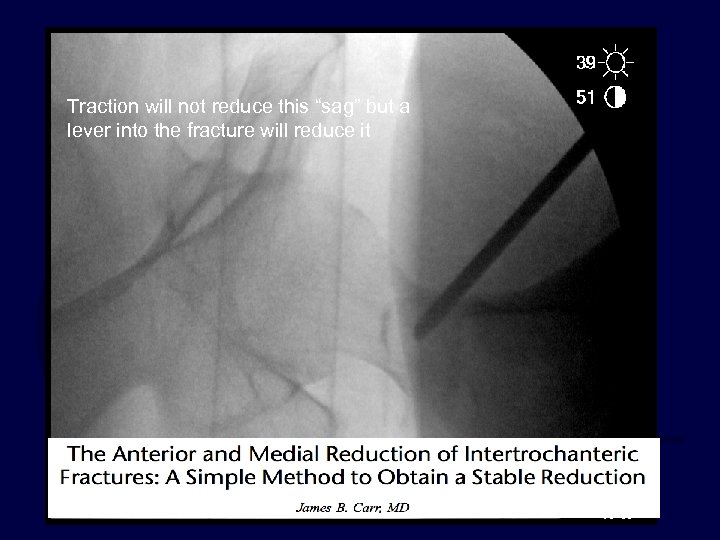

Surgeon controlled factor Fracture Reduction · Discuss sequence of closed reduction steps · Consider adjuncts to fracture reduction Crutch… elevator… joystick…. etc. Lever technique– read this article:

Traction will not reduce this “sag” but a lever into the fracture will

Traction will not reduce this “sag” but a lever into the fracture will reduce it

Surgeon controlled factor Fracture Reduction The AP view before and after lever redution: the medial cortex is restored